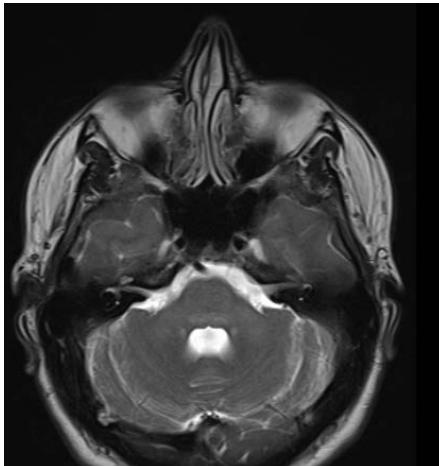

We report a rare case of Wilson’s Disease with neurologic features in a 31-year-old man. This disease consists of a disturbance of copper metabolism secondary to a mutation in the gene responsible for encoding the tissue transporter and the enzyme that incorporates the excess element into bile, generating toxic accumulation in the liver, cornea, and central nervous system. According to his wife, the patient had been treated for an unspecified mood disorder. The clinical picture was characterized by depressive mood, anhedonia, and anxiety. He had his first seizure episode on December 3rd, 2021. He progressed with dysarthria, ataxic gait, dystonia of the right-hand flexor muscles, and intermittent urinary incontinence. Marked worsening was observed after the diagnosis of COVID-19 in February 2022. At the clinical evaluation on March 24th, risorius muscle dystonia (risus sardonicus), resting tremor, and Kayser Fleischer rings at slit-lamp examination was also noted.

Detailed image from a research journal sample.